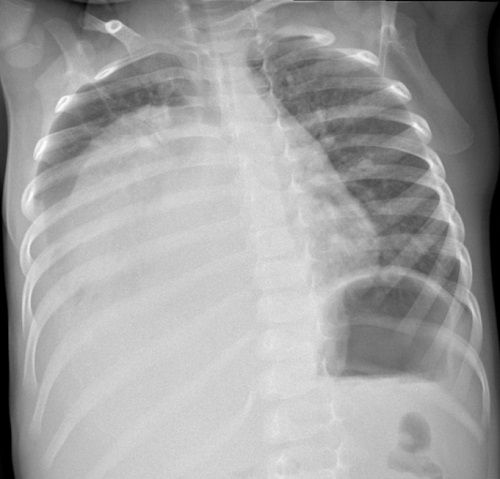

En el paciente de 23 meses, al inicio del cuadro se realiza prueba broncodilatadora con salbutamol con respuesta inicial y continúa tratamiento durante una semana. Presenta distrés progresivo con hipoventilación asimétrica e hipoxemia, por lo que se realiza radiografía de tórax, en la que se objetiva una gran masa torácica con desplazamiento de estructuras y derrame pleural asociado (Figura 1).

| Figura 1. Radiografía de tórax, en la que se objetiva una gran masa torácica con desplazamiento de estructuras y derrame pleural asociado |